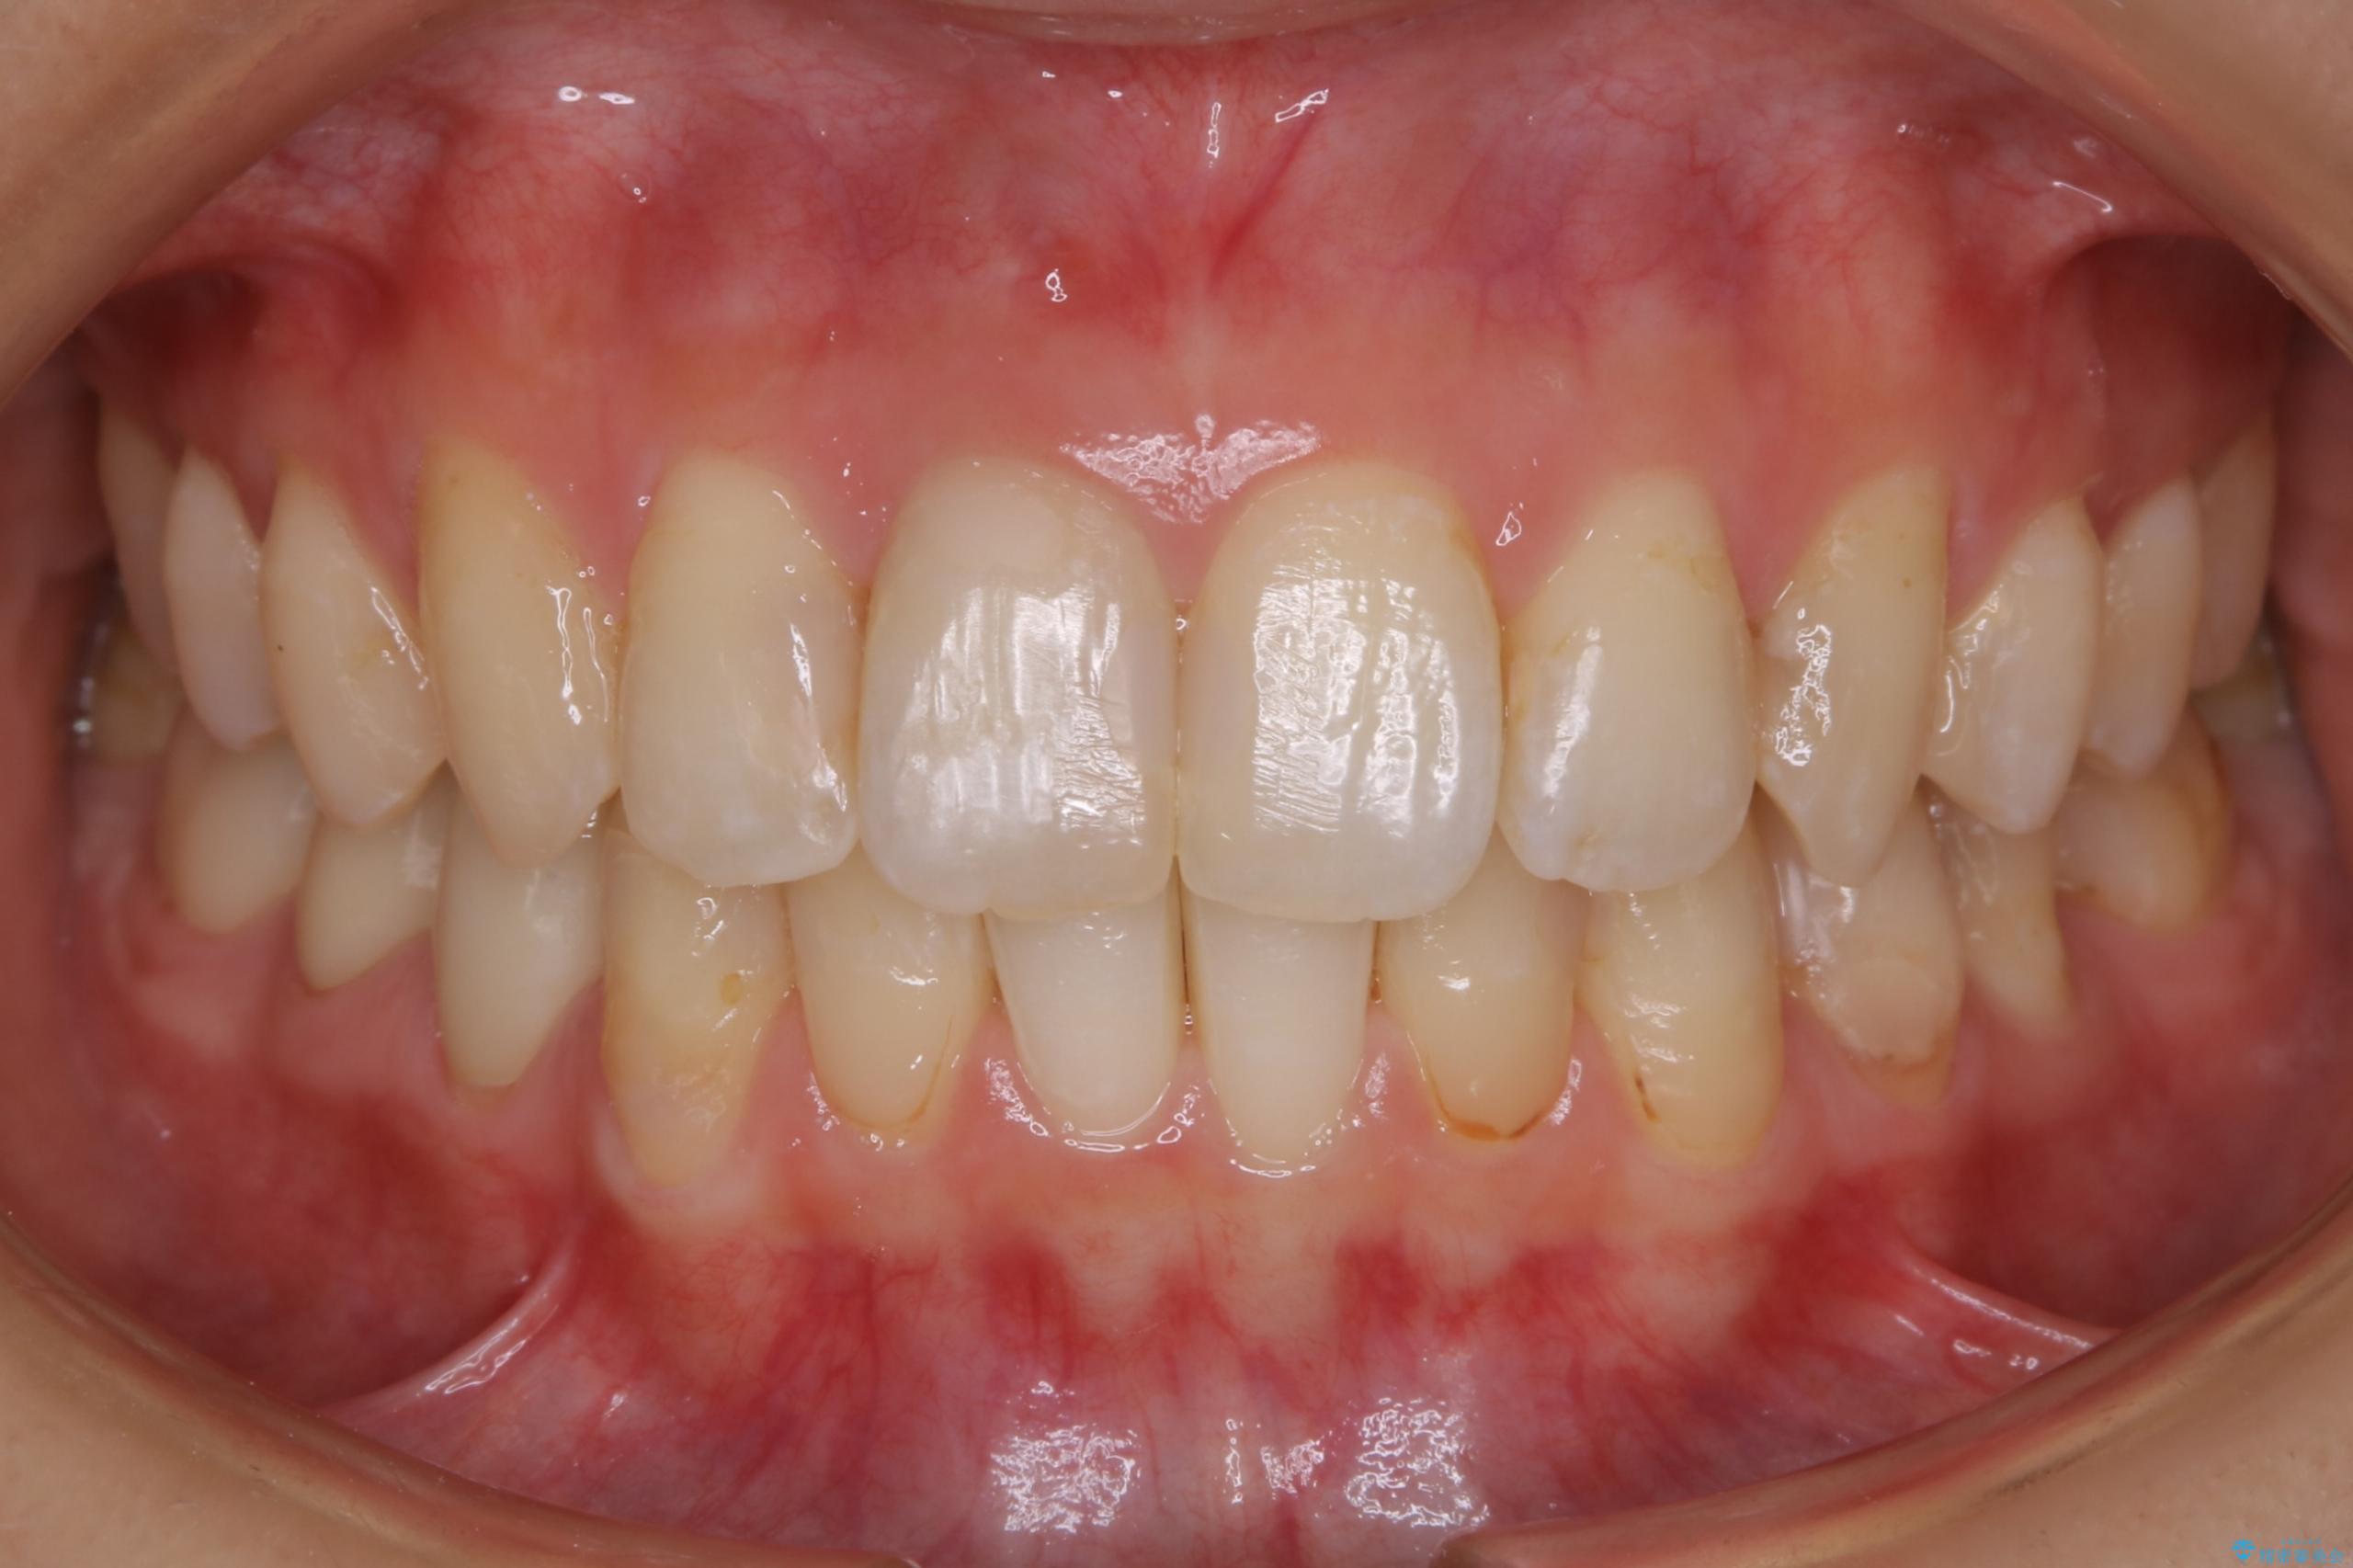

治療後

20代 女性 非抜歯で歯列をコンパクトに20代 女性 非抜歯で歯列をコンパクトに20代 女性 非抜歯で歯列をコンパクトに